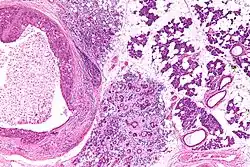

Their histologic appearance is similar to ductal breast carcinoma.

Very high mag.